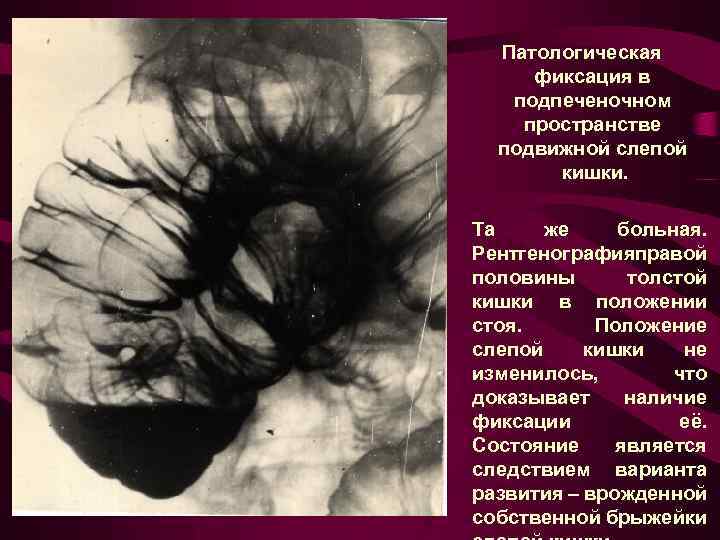

Патологическая фиксация в подпеченочном пространстве подвижной слепой кишки. Та же больная. Рентгенографияправой половины толстой кишки в положении стоя. Положение слепой кишки не изменилось, что доказывает наличие фиксации её. Состояние является следствием варианта развития – врожденной собственной брыжейки